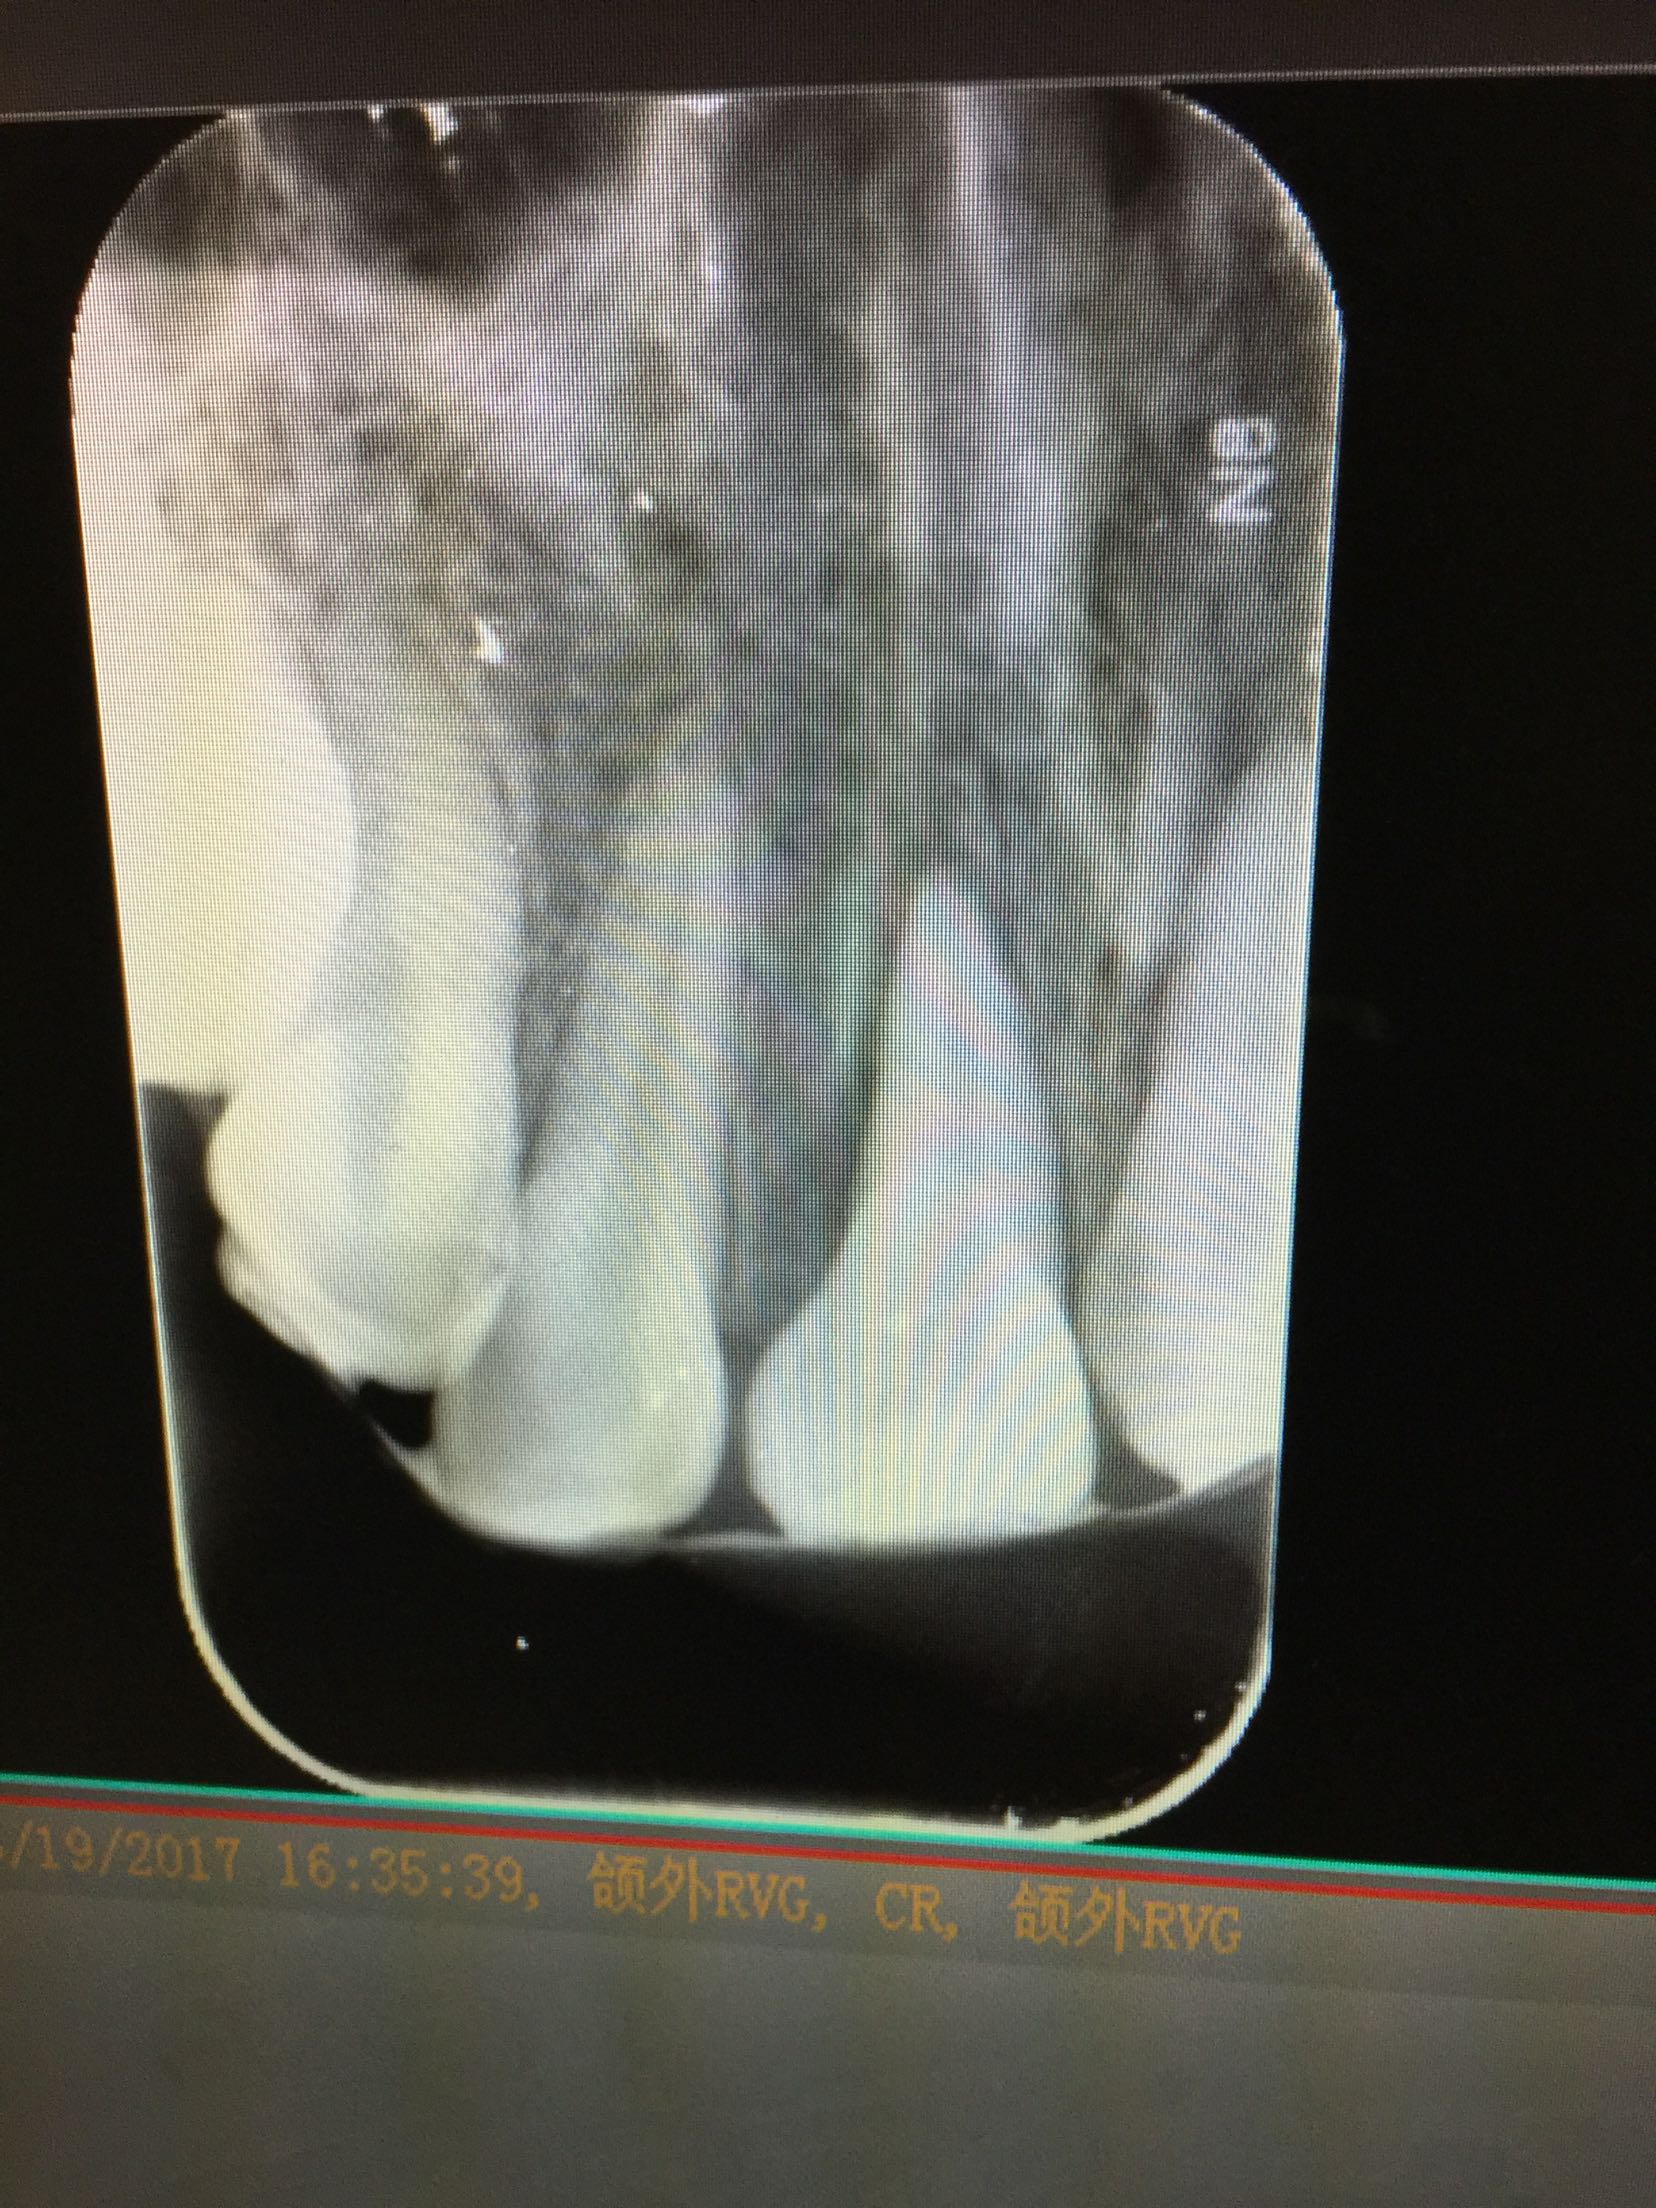

检查:11,21牙舌侧移位,不松,22牙腭侧折裂至龈下,折裂片松动III度,叩+,咬合关系紊乱。 检查:ct示11.21牙脱位伴牙槽骨骨折,22牙腭侧折裂位于牙槽脊顶下。

诊断:11牙21牙侧向移位 22牙复杂冠根折 上颌骨骨折 治疗计划:11,21牙请颌外会诊 22牙拔除折裂片后试情况制定下一步治疗计划。 请颌外会诊上颌骨骨折 治疗:患者于外科行上颌骨骨折固定求及拔除22牙折裂片后行13-23松牙固定术后。来我科行11.21.22牙根管治疗术。开髓后清扩,消毒,封veta-pex。两周后复诊。 复诊,诊间无不适。试主尖